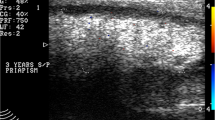

Corporal fibrosis is a process that involves excessive deposition of scar tissue in response to infection, trauma, or ischemia. It does not occur merely as a result of previous IPP surgery. Excessive development of corporal fibrosis is certain after extraneous and disastrous events such as priapism or the removal of a device for infection. The usual surgical planes and spaces are obliterated by proliferation of scar both in the tissues overlying the corpora and the space within the corpora previously occupied by erectile tissue. To maximize success, specialized instruments, downsized cylinders, and lots of experience are necessities. Prosthetic urology produces, for the most part, happy patients. Fibrosis guys, to a man are not happy. Let the expert have the unhappy patient!